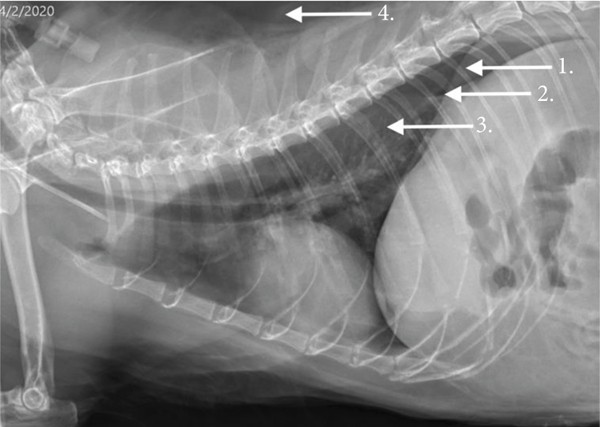

Diagnosticul incepe de obicei cu un examen fizic, in timpul caruia veterinarul poate observa dificultati de respiratie sau alte simptome. In plus, medicul veterinar poate folosi un stetoscop pentru a asculta respiratia animalului – in cazul unui pneumotorax, sunetele respiratorii normale pot fi diminuate sau absente. Pentru a confirma diagnosticul, veterinarul poate decide sa efectueze o radiografie toracica sau o ecografie, care pot arata prezenta aerului in spatiul pleural.